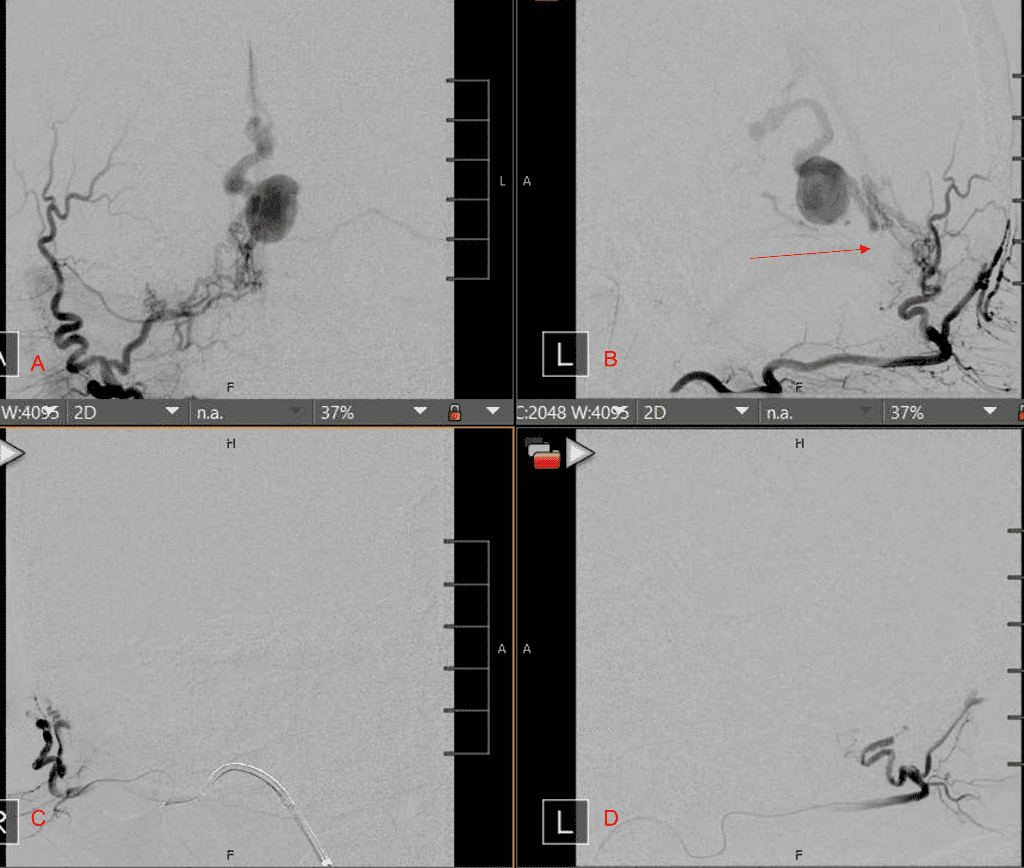

Figure 3. Right ECA AP and Lateral angiograms Pre (A and B) and Post NBCA embolization (C and D) Demonstrate near complete obliteration of right Occipital and Middle Meningeal Artery Fistulas

Embolization was successful at immediately reducing the pressure into the Aneurysmal Varix with greater than 90% reduction in A-V shunts. After an intensive period of critical care monitoring and care for her initial brain hemorrhage, she made a near complete recovery with mild intermittent left sided paresthesias and generalized deconditioning. After receiving inpatient and outpatient Acute Rehabilitation, Physical, and Occupational therapy, she completely recovered all of her Activities of Daily Living (ADLs) at 3 months and achieved an modified Rankin Scale (mRS) of 0. On follow-up angiography, small residual low flow A-V shunts were identified and targeted for Gamma Knife Radiosurgery (Figure 5 and 6).